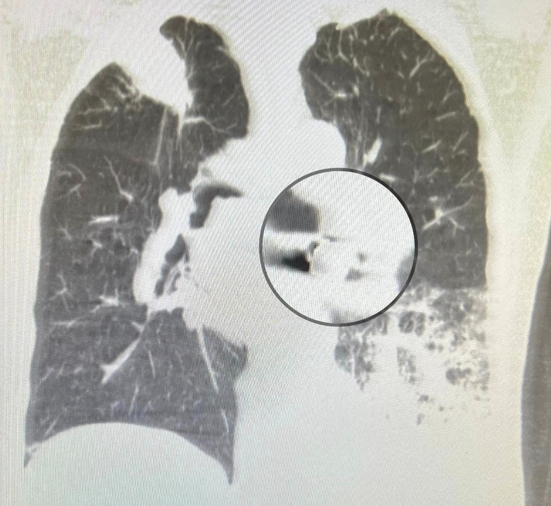

老人應該預防跌倒與嗆到才能延長壽命。 年紀大吞嚥困難常嗆到而不敢吃,產生營養不良。老是嗆入而產生吸入性肺炎而老是要住院治療,以前為了延長壽命減少嗆而接受插鼻胃管進食。但是現在為人性尊嚴與享受美食反對插鼻胃管,所以吸入性肺炎或意外嗆到而死案例增加。年紀大吃東西要小心 常常噎到甚至嗆進呼吸道。因為喉部肌肉萎縮與神經反射遲緩,食道蠕動較差所以導致吞嚥困難且易嗆進呼吸道(大的異物如假牙、骨頭等)而嚴重卡在在大氣管導致猝死。若中小異物卡在支氣管會產生塌陷與阻塞性肺炎,若睡覺口水嗆到至肺泡產生局部發炎,若是多次嗆至肺泡多次發炎產生肺纖維化。 吃東西假牙掉入左下肺支氣管產生阻塞性肺炎案例分享;九十五歲男性有抽煙史產生慢性阻塞性肺病病史且有攝護腺癌病史。最近因吃東西嗆到產生劇烈咳嗽與呼吸困難,且發現假牙不見了來院求診:胸部低劑量電腦斷層顧示右下肺有異物與阻塞牲肺炎(見圖)。緊急支氣管鏡檢並移出此異物。